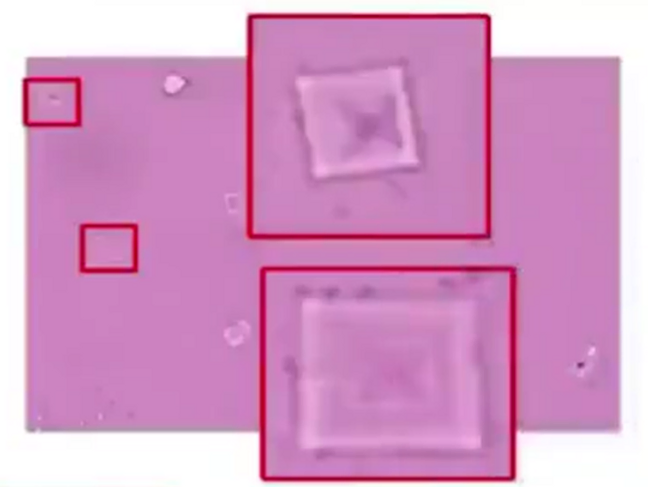

Comparison of crystals in the blood and in the vaccine; on the left, crystalline formations are found in the blood of test subjects vaccinated with Comirnaty (BioNTech/Pfizer), the images on the right show that these types of crystals are also found in Comirnaty vaccines. Image credit: Helen Krenn

Graphene Ferric oxide crystals (Ferromagnetic Properties) and Trypansoma cruzi parasite eggs were observed in the live capillary blood from a VAXXinated male using Brightfield, pHase contrast microscopy and confirmed with UV absorbance and Fluorescence Spectroscopy, Scanning Electron Microscopy, Transmission Electron Microscopy, Energy Dispersive Spectroscopy, X-ray Diffractometer and Nuclear Magnetic Resonance instruments. – Copyright Hikari Omni Media – Robert O. Young MSc, DSc, PhD, Naturopathic Practitioner – 2021